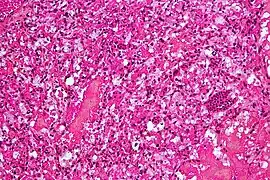

Micrograph of cerebellar hemangioblastoma. HPS stain. -

Micrograph of cerebellar hemangioblastoma. HPS stain.